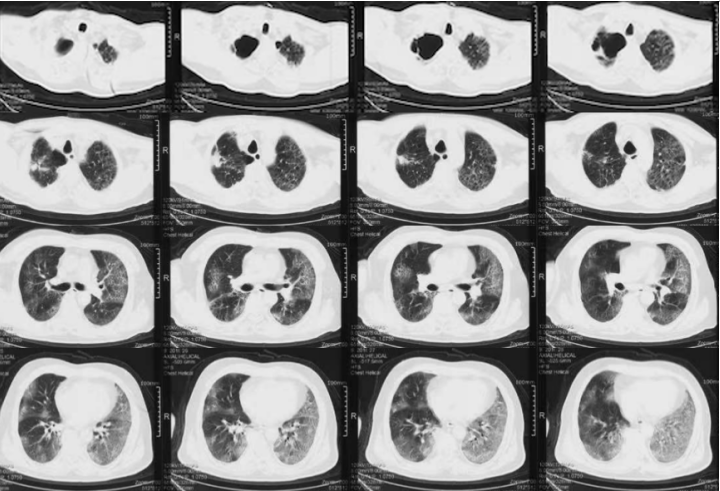

注:VV-ECMO参数:2700~3045 r/min,BF 3.4~3.9 L/min,GF 3 L/min,FiO2 1.0影像:下图分别是患者起病14、21及25天的胸部CT对比,在抗炎之后,患者肺部实变部分有明显吸收,且范围缩小。患者影像学变化过程:单纯磨玻璃影→实变伴磨玻璃影→实变、磨玻璃影伴牵拉性支气管扩张。综合上述,抗炎治疗后患者炎症指标下降、氧合改善、影像学吸收,综合判断抗炎治疗有效。患者在插管后出现了严重的酸中毒,在增加分钟通气量后,仍难以改善高碳酸血症和低氧,故选择ECMO支持。插管后3天,为了加强气道管理予气管切开。在ECMO支持7天后,复查胸部CT发现少量纵隔气肿,故于当天下调PEEP至6 cmH2O。追溯患者发生气压伤的原因,可能与过高的呼吸驱动有关,上调瑞芬太尼和丙泊酚的泵入速度,加深镇痛镇静。2023年1月1日患者PaO2较前稍有下降,查体双肺湿啰音,无皮下气肿及气胸表现,所以再次上调PEEP至8 cmH2O。经过上述处理,患者呼吸频率仍在25次/min左右,潮气量约为500 ml。1月3日患者出现寒战,ECMO抖管,再次复查胸部CT发现纵隔气肿较前加重,下调PEEP至4 cmH2O。在瑞芬太尼镇痛基础上应用丙泊酚+咪达唑仑双联镇静,患者呼吸频率下降,维持在20次/min左右,潮气量降至400 ml。